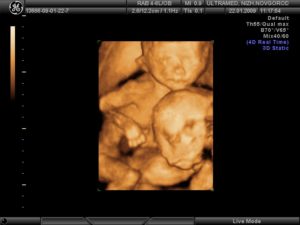

Именно в этот период происходит опущение яичек мальчиков в мошонку. В буквальном смысле малыш растет не по дням, а по часам, прибавляя более 1,0 г к своему весу. Если мама пропустит время приема пищи, он посасывает свой большой пальчик – это явление можно четко наблюдать на трехмерном (3D) или четырехмерном (4D) УЗИ 3 триместра.

Трехмерное УЗИ при беременности на поздних сроках дает возможность увидеть мельчайшие детали в развитии частей тела и органов ребенка. Высококачественное объемное изображение позволяет не только провести точную диагностику, но и сделать фотоснимки и видео внутриутробной жизни малыша.

С помощью 3D УЗИ возможно определить отклонения, которые порой не видны на обычном скрининге. Исследование является платным.

4D УЗИ, которое включает четыре измерения (ширина, высота, глубина и время), позволяет записать движения малыша в реальном времени. Диагност имеет возможность записать клип на диск и предоставить запись родителям. Конечно, эта услуга, как и сам скрининг, проводится платно.

Скорее всего на предыдущих скринингах маме и папе уже сообщили, мальчик у них или девочка. На третьем исследовании им обязательно подтвердят пол ребенка.